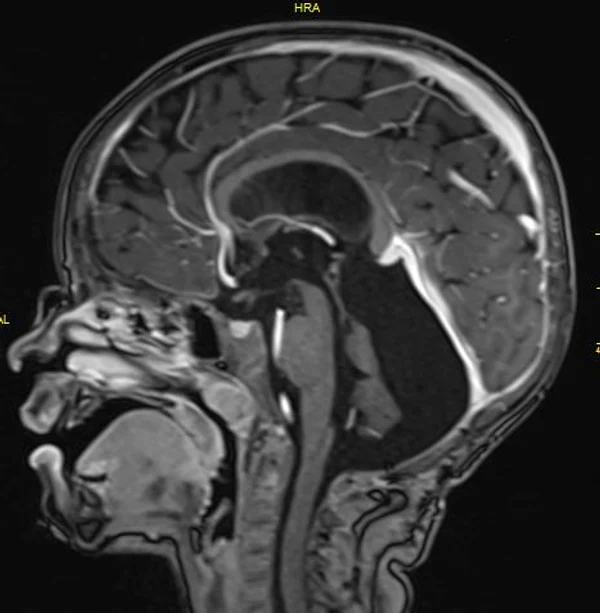

В качестве примера приведены 2 случая хирургического лечения новорожденных с врожденными опухолями головного мозга и позвоночного канала. У новорожденной девочки опухоль (хориодпапиллома) располагалась в области треугольника правого бокового желудочка (рис. 28 а, б). В возрасте 2-х недель жизни опухоль удалена. По данным МРТ головы с внутривенным введением контрастного препарата выполненной через 2 дня после операции опухоль удалена тотально (рис. 28 в). Послеоперационных осложнений не наблюдалось. У второго пациента 2-х нед. жизни врождённая опухоль (нейробластома) располагалась в позвоночном канале на уровне Th10-L3 позвонков (рис. 29 а) и распространялась в забрюшинное пространство. Клиническая картина заболевания складывалась из нижнего вялого парапареза и нарушения функции тазовых органов. Во время операции остистые отростки Th 11-L3 позвонков рассечены по средней линии. Дужки 6 данных позвонков надломлены и разведены в стороны. Опухоль располагалась экстрадурально, отделена от дорзальной поверхности дурального мешка и корешков спинно-мозговых нервов, после чего полностью удалена из позвоночного канала. Половинки дужек позвонков сведены к средней линии и сшиты между собой. Опухолевый узел в забрюшинном пространстве через 2 нед. удален онкологами. Через год после операции по данным МРТ рецидива опухоли нет (рис. 29 б). При спондилографии дефектов задней стенки и деформаций позвоночника не выявлено (рис. 29 в). Мальчик ходит, мочу и кал удерживает.